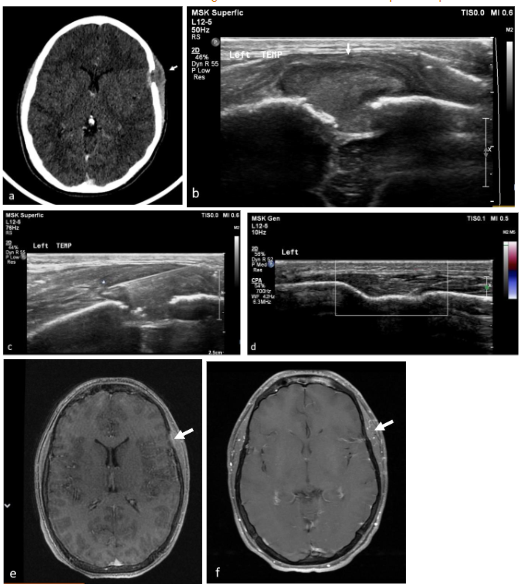

The percutaneous biopsies were performed under sonographic guidance in the US suite. The team included an experienced pediatric radiologist, US technician, a nurse, and an anesthesiologist. All cases were carried out under deep sedation without intubation. We performed sonographic-guided biopsies of lytic bone lesions of the skull and facial bones with soft tissue mass. After a thorough examination of the child, the biopsy site, positioning of the child, and the probe were chosen. Percutaneous biopsy was an option whenever there was a soft tissue bulge above the skull level and the biopsy was tangential to the skull. For the core biopsy, we used a spring-loaded core biopsy needle (Super Core Biopsy Instrument; Angiotech), 16- to 18-G caliber. Core biopsies were sent for pathologic evaluation (3 cores in most cases), molecular biology, and genetic studies as needed. During 2019, we added an onsite smear cytology to some of our biopsies.

PERCUTANEOUS BIOPSY

The median time between biopsy request and procedure was 1 day (range same day to 10 days), with 4 patients undergoing the biopsy within a day. Most procedures (8/9) were performed on hospitalized patients, with 1 performed on an outpatient basis. All procedures were conducted under deep sedation. The biopsy was diagnostic in 8 of 9 patients; the only non-diagnostic biopsy failed due to the absence of a soft tissue component adjacent to the lytic bone lesion, necessitating a subsequent surgical biopsy that was diagnostic. In two cases, on-site cytology was also performed and proved diagnostic. Core needle biopsy sizes were 18 G in 60% of cases and 16 G in 40%. The mean number of passes was 3. No complications related to anesthesia or the biopsy procedure were recorded. The mean hospital stay was 1.5 days (range same-day discharge to 3 days).

Regression of lesions occurred in 4 cases. In 2 cases regression was spontaneous, one lesion regressed completely and the second decreased in size while the patient awaited surgery, yet it was nevertheless resected. Biopsy initiated complete regression in 2 cases, the first case post-surgical biopsy and the second post FNB. The FNB case was a temporal lesion with CNS risk, yet complete regression did not require further treatment and no recurrence was reported in 17 years of follow up.

Regression of lesions occurred in 4 patients (11%). Two spontaneously and 2 post biopsies. In one of these patients, the lesion was a temporal bone lesion, a CNS risk lesion, and yet since it regressed spontaneously post FNB the patient was not treated and is disease free in 17 years follow up. Previous studies have documented similar spontaneous remissions of LCH bone lesions, including those affecting the calvaria. Regression has also been noted following biopsy, suggesting that biopsy could stimulate healing. The triggers for Langerhans cell proliferation and the factors that inhibit this process remain unclear. One hypothesis suggests that spontaneous resolution occurs due to a breakdown in self-tolerance, leading to the activation of immune effector cells that target and kill proliferating cells. A similar mechanism has been proposed for halo nevus. Consequently, some authors advocate for a short observation period as part of the initial management strategy for solitary calvarial LCH lesions to avoid unnecessary surgical intervention. Haupt et al. observed that often in isolated bone lesions, simple curettage during the diagnostic biopsy resulted in healing, therefore further intervention may not be necessary.